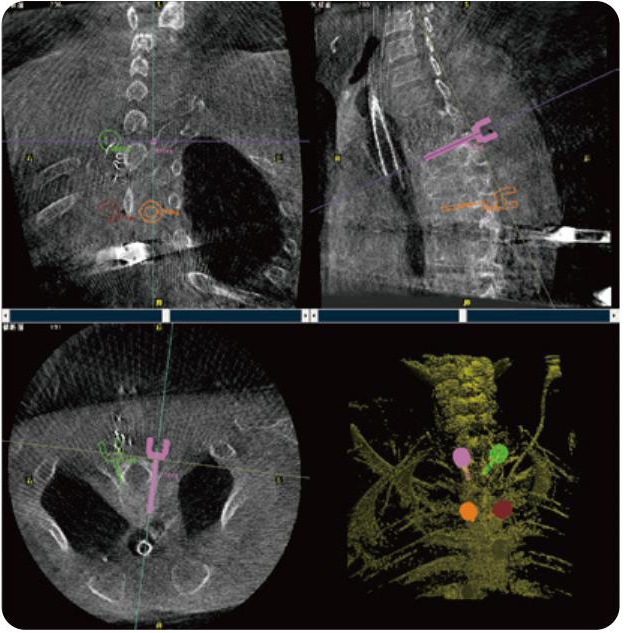

PL300B可應(yīng)用于多節(jié)段脊柱外科手術(shù),輔助醫(yī)生定位病灶部位,為脊柱外科手術(shù)(經(jīng)皮椎體成形術(shù)、椎弓根螺釘內(nèi)固定術(shù)等術(shù)式)提供術(shù)前手術(shù)流程規(guī)劃、入釘位置、角度可視化引導(dǎo),模擬仿真入釘輔助。

PL300B搭配普愛醫(yī)療自主研發(fā)生產(chǎn)的平板3D C形臂,借助一體化自適應(yīng)配準(zhǔn)( 軌跡配準(zhǔn))技術(shù),通過追蹤C形臂三維采集軌跡,自動完成圖像坐標(biāo)建立和系統(tǒng)坐標(biāo)配準(zhǔn)。配準(zhǔn)精度更高,操作步驟少,系統(tǒng)運作效率高。